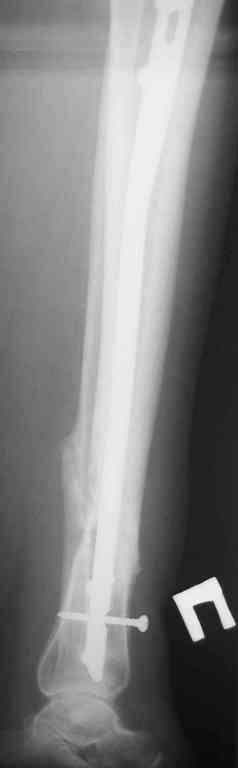

Re: Ложный сустав голени перелом штифта

Прилагаются.

Да , обсуждалась и оптимальным штифтом был выбран " Мастер" Остеомед 10 мм и винты 5 мм, но увы все наши благие намерения разбились о нашу действительность и материальные возможности больной, обращение ее в страховую компанию и т.д., вообщем выкручивались из внутренних резервов, а они были такими 9 мм штифт Остеомед, под 4 мм винты. Ограничили нагрузку. Ошиблись еще и с оценкой сращения, дали полную нагрузку+ больная поправилась на 18 кг, и вот теперь имеем , что имеем.

Действитльность и возвожности остались прежнее, во внутренних резервах есть 11 мм стержень универсальный ( реконструктивный) "Деост-CHM" много спиц и аппарат + ось конечности и отломок штифта и надежда на Ваши советы.